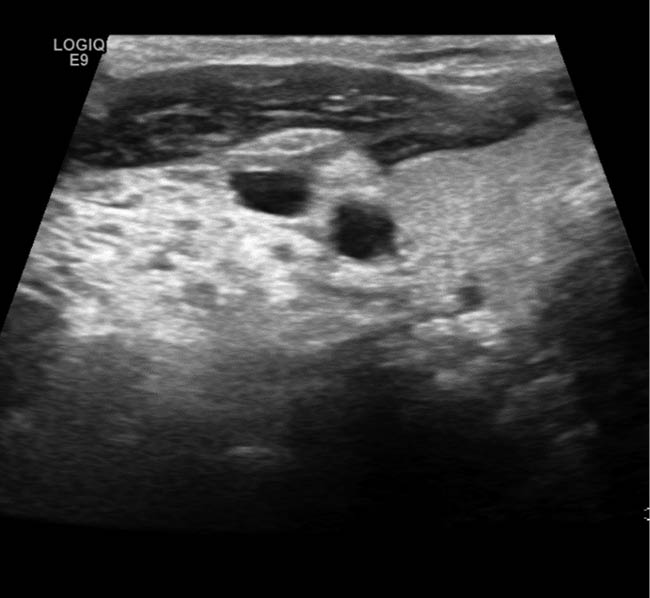

Aufgrund der symptomatischen Cholezystolithiasis nach stattgehabter akuter Cholezystitis wurde die Indikation zur elektiven laparoskopischen Cholezystektomie gestellt. An diagnostischen Verfahren wurden auswärts ein Angio-MRT (Abb. 1 – 4) des Oberbauches und eine Magnetresonanz-Cholangiopankreatikographie (MRCP) durchgeführt, welche eine Cholezystitis bei Cholezystolithiasis und eine beginnende Leberzirrhose nachweisen konnten. Im Rahmen der präoperativen Vorbereitung wurde eine Echokardiographie durchgeführt, in welchem eine Herzinsuffizienz infolge der Volumenbelastung durch die AV-Shunts i.R. des KMS und eine „Cirrhose cardiaque“ ausgeschlossen werden konnten. Als Marker einer intravasalen Gerinnungsaktivierung wurden erhöhte Prothrombinfragmente, D-Dimere und eine erniedrigte Antiplasmin-Konzentration sowie eine gesteigerte Fibrinolysekapazität detektiert. Eine sekundäre Thrombozytopenie oder eine Fibrinogen- und Faktor-XIII-Verminderung konnten ebenso wie das Vorliegen eines erworbenen von-Willebrand-Syndroms ausgeschlossen werden.

In einer hämostaseologischen Vorstellung wurde die Pausierung der Thrombozytenaggregationshemmung über 7 d unter „Bridging“ mittels niedermolekularem Heparin und eine medikamentöse Hemmung der Hyperfibrinolyse durch Tranexamsäure bis zum 3. postoperativen Tag bzw. in Abhängigkeit von Klinik und des hämostaseologischen perioperativen Monitorings empfohlen. Als perioperative Antibiotikaprophylaxe wurde Imipenem eingesetzt. Der Kameratrokar wurde entsprechend der aus dem Angio-MRT bekannten linksseitigen Ausprägung der Gefäßmalformationen (Abb. 1 – 4) in typischer Nabelposition platziert.

Abb. 2: MRT:

A) T1 axial kutan am Arcus

B) T1 axial – Befund am

M. latissimus dorsi

C) T1 axial – Hauptbefund an der hinteren Axillarlinie

D) T2 coronar – M.-latissimus-dorsi-Linie

E) T2 koronar – Hauptbefund an der hinteren Axillarlinie

F) T2 koronar – kutan am Arcus